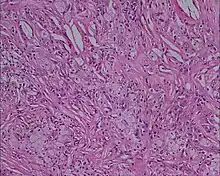

Xanthoma tuberosum

Xanthoma tuberosum (also known as tuberous xanthoma) is characterized by xanthomas located over tuberosity of the joints.[2]: 530